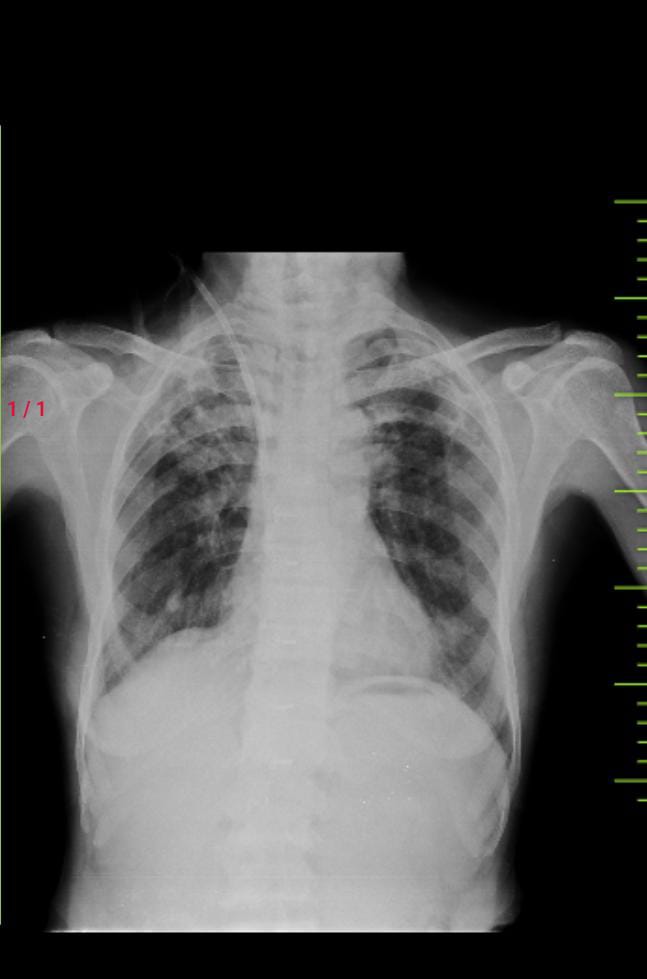

History of pulmonary TB 30 years back